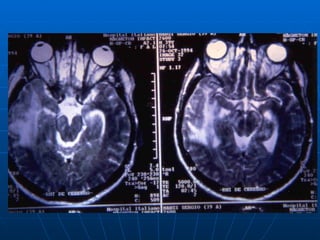

PATOGENIA 1. El 70 % es por reactivación de virus latentes  en el ganglio trigémino, que avanzan por vía retrógrada a las áreas frontotemporales del cerebro. 2. En el 30 % son primoinfecciones  en las que el VHS asciende desde la nasofaringe, por los nervios olfatorios y llega a los lóbulos frontal y temporal. Las lesiones tienen predilección por las áreas frontal y temporal

PATOGENIA 1. El70 % es por reactivación de virus latentes en el ganglio trigémino, que avanzan por vía retrógrada a las áreas frontotemporales del cerebro. 2. En el 30 % son primoinfecciones en las que el VHS asciende desde la nasofaringe, por los nervios olfatorios y llega a los lóbulos frontal y temporal. Las lesiones tienen predilección por las áreas frontal y temporal